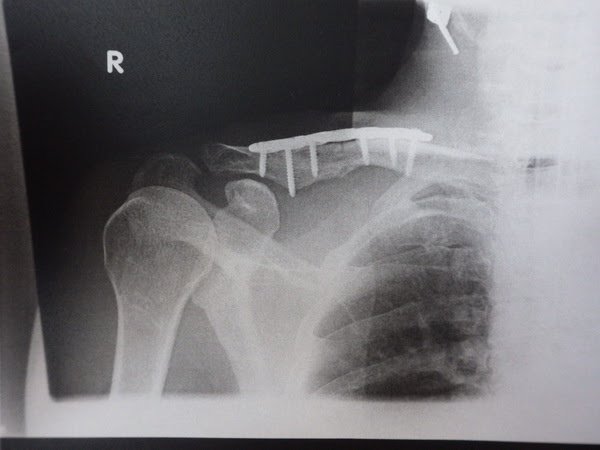

Title Adobe Photoshop PDF Created Date 8/4/10 AM右鎖骨骨折・・・抜釘、まとめ 早いもので、昨年の8月末に右肩の鎖骨骨折をしまして。 その後に固定プレートの手術をしてから、1年2カ月の歳月が経とうとしています。 レントゲンにはこう写ってまして。 それが! スーパードクターXによる手術後の製品情報|HOYA Technosurgical株式会社 本品は、チタン合金製の肩鎖関節脱臼・鎖骨遠位端骨折用プレートシステムです。 合併症軽減、強固な固定を目指して開発されたロッキングプレートです。 症例に応じて2種類から選択できます。

鎖骨遠位端骨折 Tadpole Plate 製造販売承認番号:BZX 販売名:メイラ鎖骨ロッキングプレート 材質:チタン合金/プレート鎖骨骨折手術の一年後に固定していたプレートを外す手術を受けた。 意識療法士まさよ施術コンテンツ一覧 はじめての方へ / 施術内容詳細 / お客様の声 / アクセス方法 / ご予約・お問い合わせ 鎖骨骨折を手術療法で過ごした1年間 1年前の1月18日に鎖骨を骨折した。 チタンプレートとボルトで折れた骨を固定する手術療法を選択。 骨折は治癒に年単位かかる と言われ、プレートを抜くのは約1年後を覚悟していたが幸い少し早めに完治し1年後は

1 day ago 17日、藤田菜七子騎手は新潟2レースの騎乗中に負傷し、第5レース以降の5鞍をキャンセル。 jraは左鎖骨骨折と診断されたと発表した。 先日プレート除去手術をしたばかり 菜七子騎手は昨年2月の小倉競馬で落馬し左鎖骨を骨折、先日21日に手術した際のプレート除去手術を行ったばかり⑤鎖骨骨折の3%は血気胸や同側の肋骨骨折を合併しているので,注意を要する. た.プレート固定術を施行した. 烏口突起骨折で肩鎖関節脱臼を合併した場合は手術が必要である. 肩峰骨折で肩峰が下方に転位した場合と肩峰棘骨折の基部より外側鎖骨骨幹部骨折に対する手術治療成績 時計台病院 整形外科 木村明彦 福島 直 岡崎俊一郎 札幌医科大学 保健医療学部理学療法学科 青木光広 Keywords:Fracture of clavicle(鎖骨骨幹部骨折) Open reduction(手術療法) Plate fixation(プレート固定)